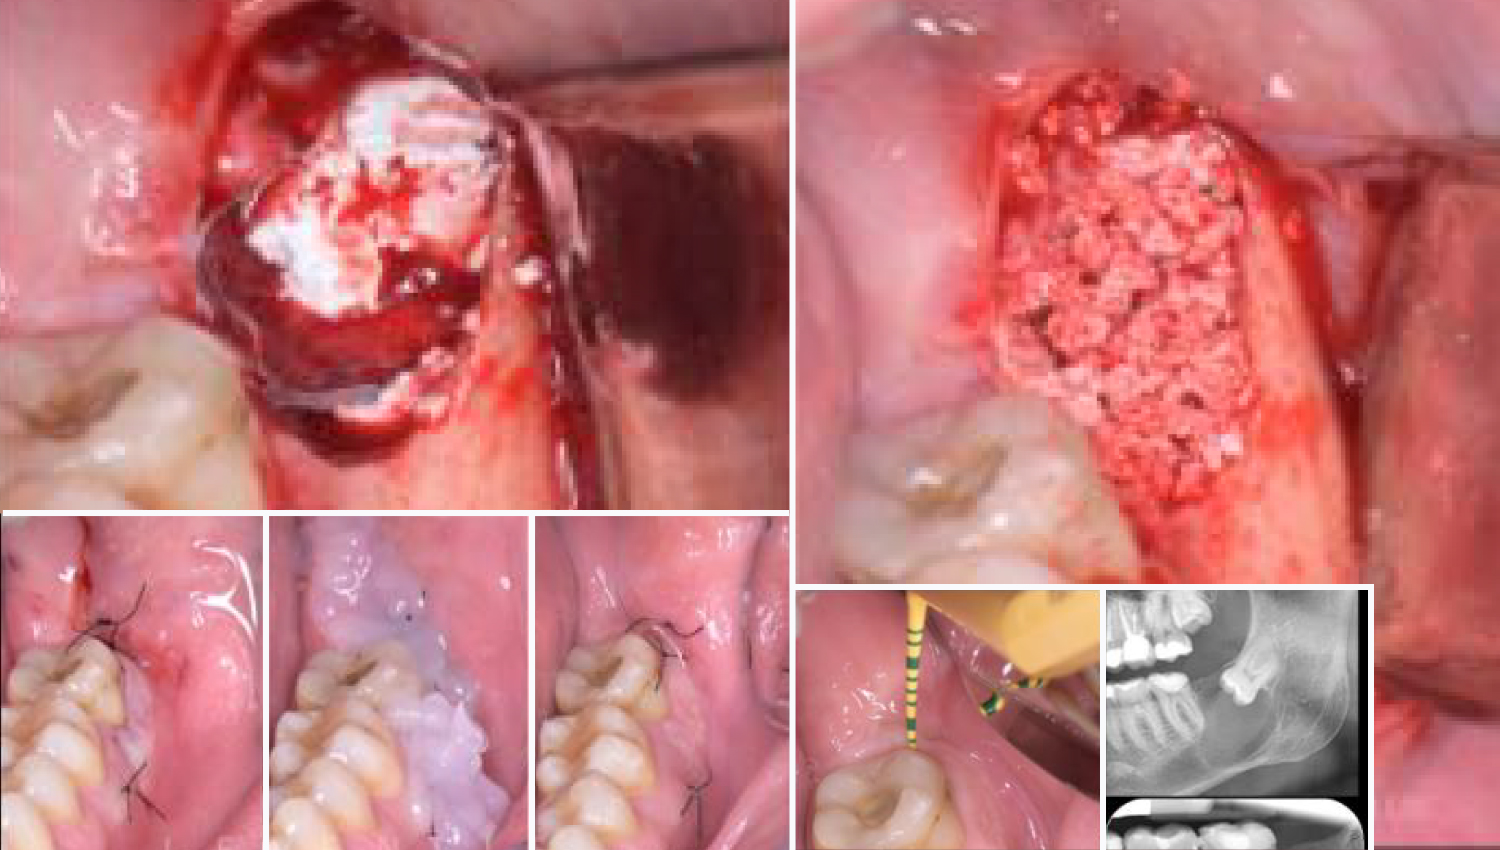

1.Initial Clinical view.

2. Initial periapical x-ray.

3. Surgical removal of an impacted third molar and removal of the associated dentigerous cyst.

4. Reconstruction of the bone defectusing Powerbone Putty and Crunch.

5.Grafted with Powerbone Dental Putty and PowerBone granules.

6.Clinical and radiological views 6 months post-operaticely. Healthy periodontal tissues wiht no bleeding on probing and < 3mm probing depth on the distal aspect of the second molar. The area is covered with keratinized soft tissues, and the architecture of the ridge is adequately restored.The main concern and objective was to fully regenerate the bone defect distally to the second molar, to prevent furhet bone loss and periodontal defects distally to the second molar.

7. Post-operative course.